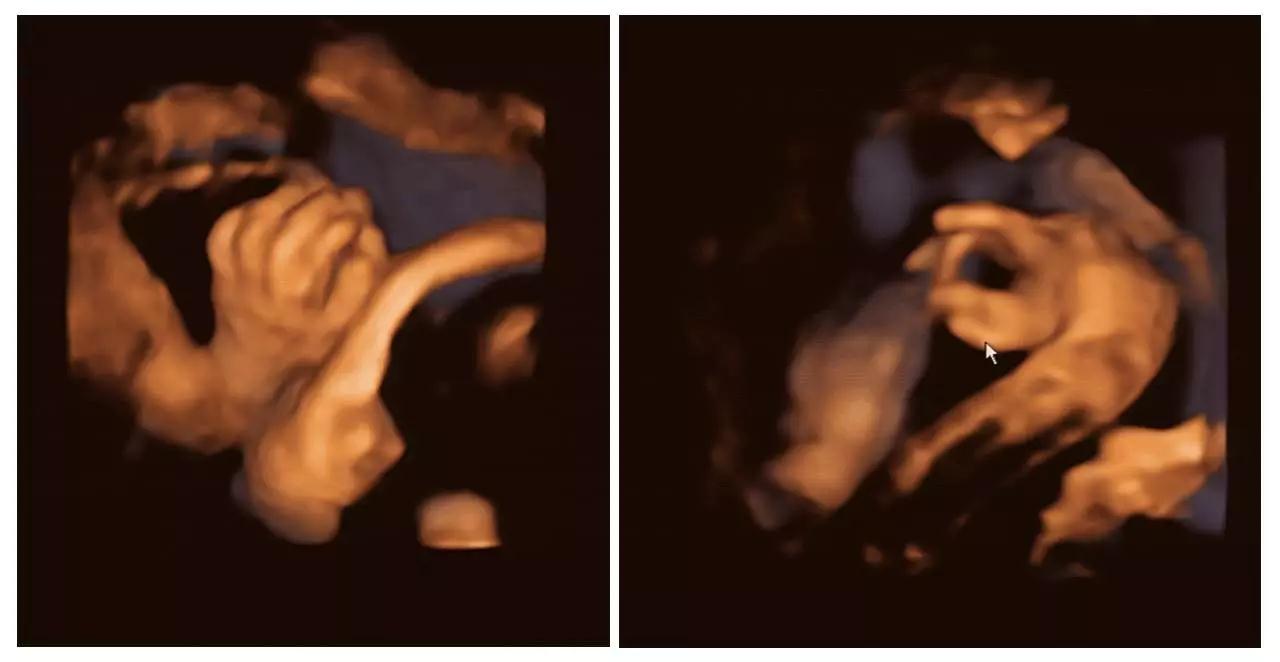

在Carissa怀孕25周的次孕检中,她在四维彩超(四维彩超)视频中发现,自己的个女儿首先亲吻了另个女儿的胸口,然后她们慢慢接近,后竟然相互用嘴亲吻!

看到这相亲相爱的幕,让准妈妈的心都要融化了,她说:“我不知道如何解释这个事情,但是看到她们这么亲近,真是太好了。”小生命真的很神奇,原来她们还没出生就已经学会接吻了。太可爱啦!祝愿这两个萌宝健康地出生!

夫妇俩给两个女儿取名为Isabella和Callie。妈妈Carissa把图像照片上传到了社交网站上。她在其中张照片中写道,Isabella在姐姐Callie的脸颊上印了个吻。在另张照片中,她写道,在这刻她很感恩,迫不及待地想要认识这两位珍贵的公主。

大自然将亲吻作为崇高的感情表达赋予给了生灵。也许是Isabella和Callie在妈妈Carissa腹中,感受到了彼此的血脉亲情,用温柔吻许下今生照顾彼此的诺言。